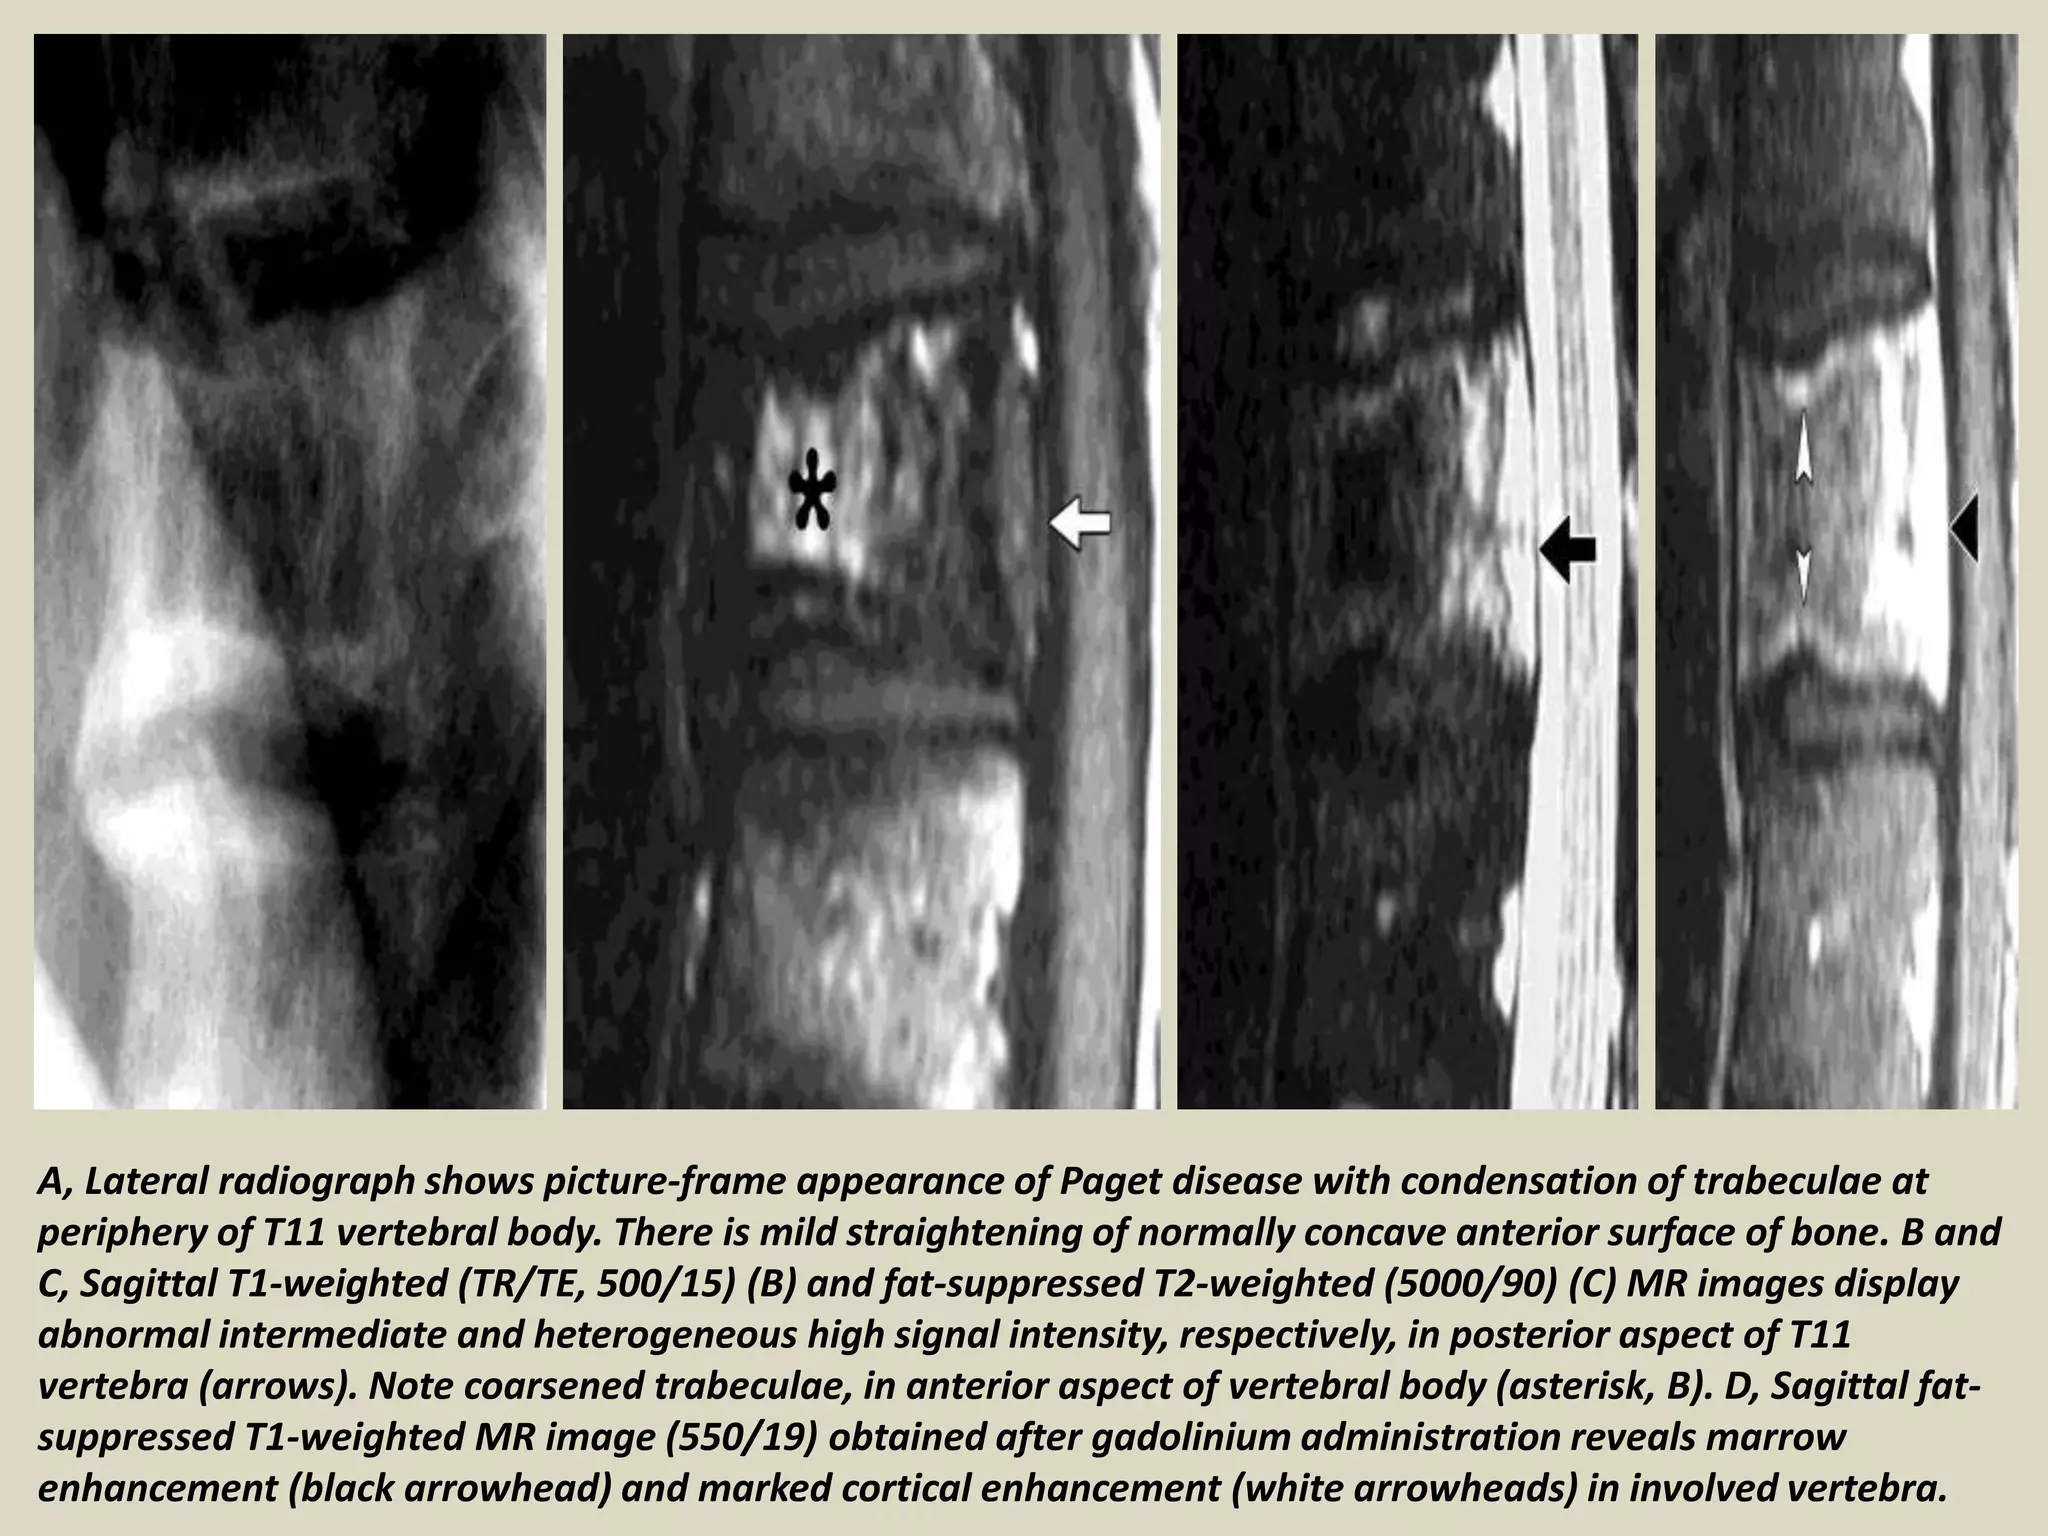

A, Lateral radiograph shows picture-frame appearance of Paget disease with condensation of trabeculae at

periphery of T11 vertebral body. There is mild straightening of normally concave anterior surface of bone. B and

C, Sagittal T1-weighted (TR/TE, 500/15) (B) and fat-suppressed T2-weighted (5000/90) (C) MR images display

abnormal intermediate and heterogeneous high signal intensity, respectively, in posterior aspect of T11

vertebra (arrows). Note coarsened trabeculae, in anterior aspect of vertebral body (asterisk, B). D, Sagittal fat-

suppressed T1-weighted MR image (550/19) obtained after gadolinium administration reveals marrow

enhancement (black arrowhead) and marked cortical enhancement (white arrowheads) in involved vertebra.

A, Lateral radiographshows picture-frame appearance of Paget disease with condensation of trabeculae at periphery of T11 vertebral body. There is mild straightening of normally concave anterior surface of bone. B and C, Sagittal T1-weighted (TR/TE, 500/15) (B) and fat-suppressed T2-weighted (5000/90) (C) MR images display abnormal intermediate and heterogeneous high signal intensity, respectively, in posterior aspect of T11 vertebra (arrows). Note coarsened trabeculae, in anterior aspect of vertebral body (asterisk, B). D, Sagittal fat- suppressed T1-weighted MR image (550/19) obtained after gadolinium administration reveals marrow enhancement (black arrowhead) and marked cortical enhancement (white arrowheads) in involved vertebra.